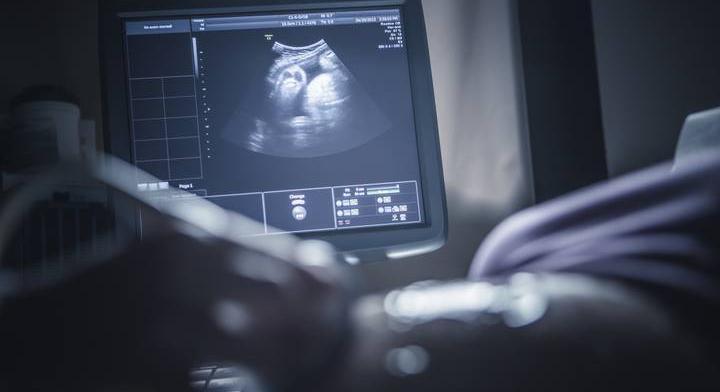

18 év sikertelen próbálkozás után az AI segítségével lehet anya ez a nő

A hagyományos módszerek többször kudarcot vallottak, a mesterséges intelligencia azonban segített a nőnek teherbe esni.